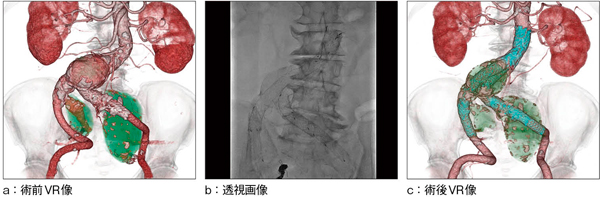

■症例2 EVAR(腹部大動脈ステントグラフト内挿術)

腹部大動脈瘤50mm,左総腸骨動脈瘤40mm,右内腸骨動脈瘤32mm,左内腸骨動脈57mmを指摘される。 前日に左内腸骨動脈コイル塞栓施行。 右内腸骨動脈コイル塞栓術を施行し,ステントグラフトを留置。